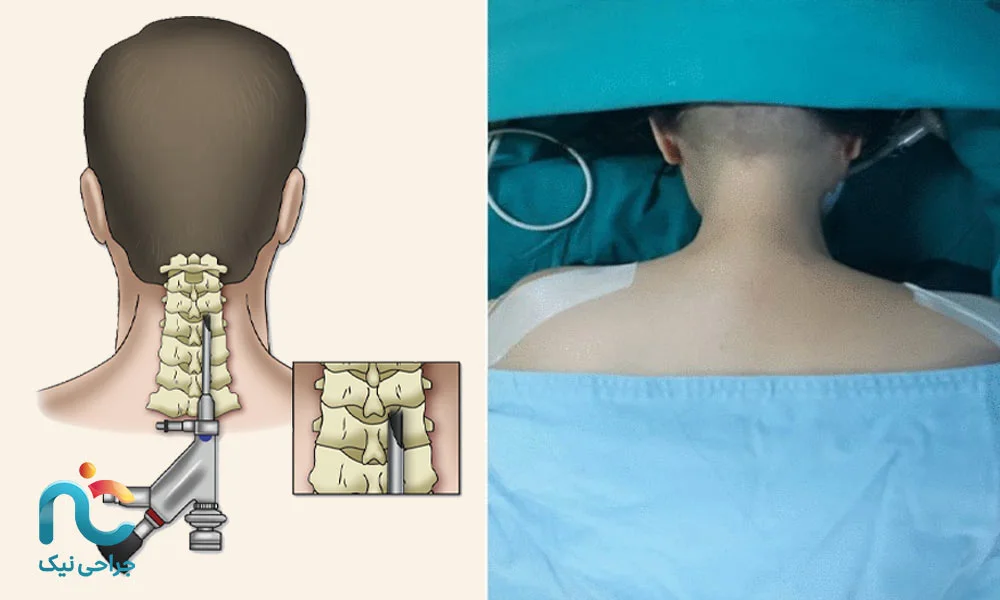

۲. روش خلفی (Posterior Approach)

در این حالت، جراح از پشت گردن وارد ناحیه آسیبدیده میشود. این مسیر زمانی انتخاب میشود که بیرونزدگی دیسک به سمت عقب یا کنار باشد و فشار روی ریشههای عصبی بیشتر از پشت ایجاد شده باشد. در این روش، عضلات کمی کنار زده میشوند اما با کمک اندوسکوپ آسیبی به آنها وارد نمیشود.